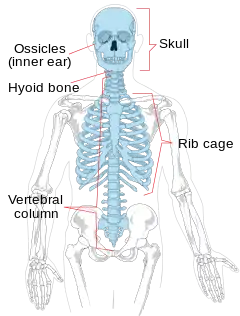

Diagram of the axial skeleton

The Axial Skeleton is a division of the human skeleton and is named because it makes up the longitudinal axis of the body. It consists of the skull, hyoid bone, vertebral column, sternum and ribs. It is widely accepted to be made up of 80 bones, although this number varies from individual to individual.